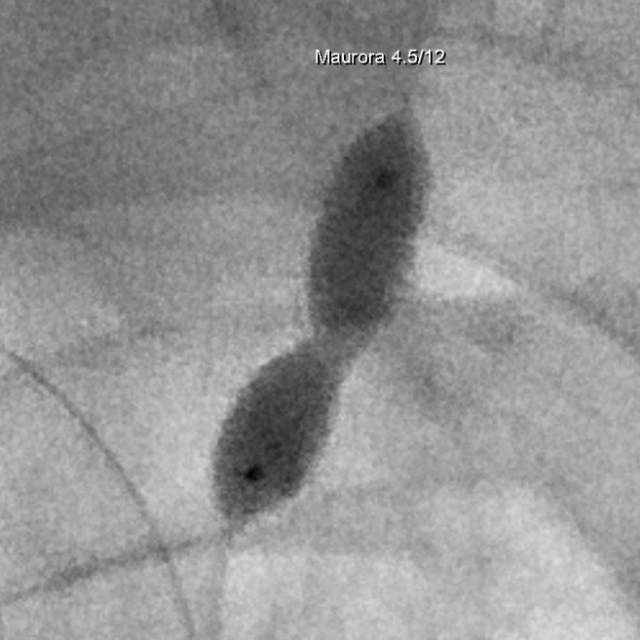

和家属商量后,我们采用全球首款椎动脉专用药物洗脱支架(Maurora)成功精准切线位植入,消除了这个“卡脖子”的狭窄……

按照说明书的介绍,与裸支架相比,Maurora可以降低再狭窄率66/……